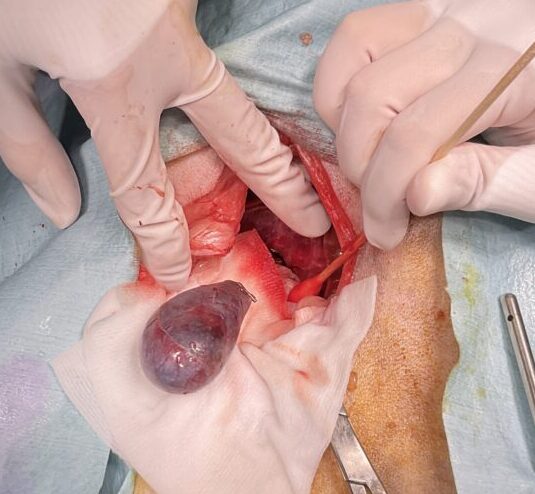

胆嚢粘液嚢腫

高齢犬の定期検診で胆嚢粘液嚢腫が発見されたため、手術が必要か相談したいとのことで紹介来院されました。

血液検査では肝数値の上昇はなく現時点では症状もありませんが、今後さらに高齢になり症状が出てからだとリスクが上がるため手術を行うこととなりました。

待機手術ではなく、胆嚢破裂などの緊急手術では周術期リスクが高くなります。